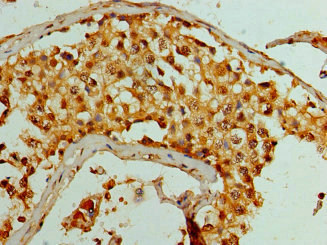

Immunohistochemistry of paraffin-embedded human testis tissue using CSB-PA525314HA01HU at dilution of 1:100